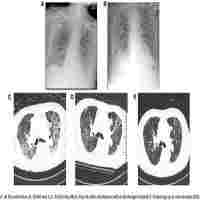

| Abstract | Background The study evaluates the impact of the time between commencing non-invasive ventilation (NIV) support and initiation of venovenous extracorporeal membrane oxygenation (VV-ECMO) in a cohort of critically ill patients with coronavirus disease 2019 (COVID-19) associated acute respiratory distress syndrome (ARDS). Methods Prospective observational study design in an intensive Care Unit (ICU) of a tertiary hospital in Barcelona (Spain). All patients requiring VV-ECMO support due to COVID-19 associated ARDS between March 2020 and January 2022 were analysed. Survival outcome was determined at 90 days after VV-ECMO initiation. Demographic data, comorbidities at ICU admission, RESP (respiratory ECMO survival prediction) score, antiviral and immunomodulatory treatments received, inflammatory biomarkers, the need for vasopressors, the thromboprophylaxis regimen received, and respiratory parameters including the length of intubation previous to ECMO and the length of each NIV support (high-flow nasal cannula, continuous positive airway pressure and bi-level positive airway pressure), were also collated in order to assess risk factors for day-90 mortality. The effect of the time lapse between NIV support and VV-ECMO on survival was evaluated using logistic regression and adjusting the association with all factors that were significant in the univariate analysis. Results Seventy-two patients finally received VV-ECMO support. At 90 days after commencing VV-ECMO 35 patients (48%) had died and 37 patients (52%) were alive. Multivariable analysis showed that at VV-ECMO initiation, age (p = 0.02), lactate (p = 0.001), and days from initiation of NIV support to starting VV-ECMO (p = 0.04) were all associated with day-90 mortality. Conclusions In our small cohort of VV-ECMO patients with COVID-19 associated ARDS, the time spent between initiation of NIV support and VV-ECMO (together with age and lactate) appeared to be a better predictor of mortality than the time between intubation and VV-ECMO. |